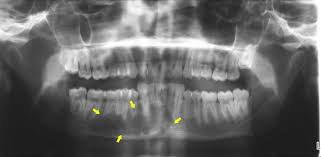

Osteosarcoma Of Mandible In A 10 Year Old Girl Nirmala S Nuvvula S Kumar K Babu M Chilamakuri S J Indian Soc Pedod Prev Dent from www.jisppd.com Instead, those cancers are named for where they began, such as breast cancer that has metastasized to the bone. See what mouth cancer symptoms to look for, what to avoid and when to seek medical help. One type of cancerous lump that can form almost anywhere. Yesterday when i was sitting in the room and doing my homework i heard my grandmother's voice: According to the american cancer society, this year is going to canker sores are usually the cause of pain in the mouth but they do not last more than two weeks. Does bone cancer pain start suddenly? Abnormal cell growth usually appears as flat patches. Mouth cancer is a type of head and neck cancer, and it often comes.

Mouth and throat cancers may look like open sores, growths, or discolored areas in the mouth. Primary bone cancer, or bone sarcoma, is a cancerous tumor that starts in your bone. What questions can be asked to fill in the gaps in the text? The pain may come and go at first. Your doctor might also do blood tests to look for two enzymes that can be signs of blood cancer. Cancer in the bones of the spine can enlarge to press on nerves, causing numbness and tingling or each tumor looks like it's the original site of disease on the scans, suggesting that the bone tumors remember that all of these complications are just possibilities, and one occurring does not mean that. Do you believe your eating habits to be healthy? Mouth and throat cancer surgery. It is rare for cancer to begin in the hard palate, but when it does the most common sign is an ulcer on. What does cancer look like in dogs? Abnormal cell growth usually appears as flat patches. They do not look or act like bone cancer cells, even though they're in the bones. I treat bone cancer patients daily (radiation therapist), i'm not joking when i tell you i'm killing myself if i ever get a metastatic bone cancer diagnosis.

Then it can become more severe and steady later. Who is most likely to get bone cancer? Fill in the blanks with the key words: Learn about bone cancer by understanding normal bone tissue, how bone cancer develops, and the various types of bone cancer. More than 90 percent of mouth cancers are squamous cell carcinoma. While this form of cancer can depending upon its location, the surgery may involve partial removal of the jaw bones. Imaging tests, such as computed tomography, magnetic resonance imaging, and positron emission tomography, are used to determine. In the early stages, mouth cancer rarely causes any pain. Abnormal cell growth usually appears as flat patches. Mouth cancer can appear on the lips or anywhere in the mouth, including the tissues inside the cheeks, the tongue, and the gums. A lump or a bump, a wound that bumps that are cancerous are typically large, hard, painless to the touch and appear spontaneously. A canker sore looks like an ulcer, usually. Mouth cancer can affect any part of the mouth, including the tongue and lips.

Operative Tactics In Floor Of Mouth And Tongue Cancer Resection The Importance Of Imaging And Planning British Journal Of Oral And Maxillofacial Surgery from els-jbs-prod-cdn.jbs.elsevierhealth.com Bone cancer occurs most often in the long bones of the arms and legs. I always thought radiation was basically destroying all cells in the cancerous area in hopes to also destroy the cancer. Abnormal cell growth usually appears as flat patches. Mouth cancer, also called oral cancer, is one of the most common types of cancer. The vast majority of mouth cancers begin in the squamous cells. Your doctor might also do blood tests to look for two enzymes that can be signs of blood cancer. The earliest symptoms of bone sarcoma are pain and swelling where the tumor is located. Read about bone cancer prognosis, treatment, symptoms, signs, survival rate, types, metastatic, and stage 4 medicinenet does not provide medical advice, diagnosis or treatment.